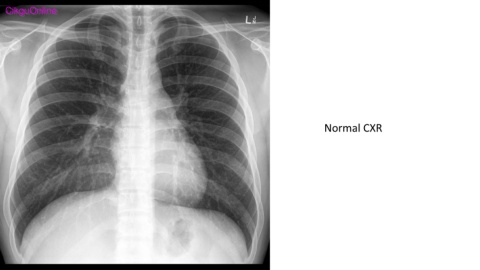

Normal CXR